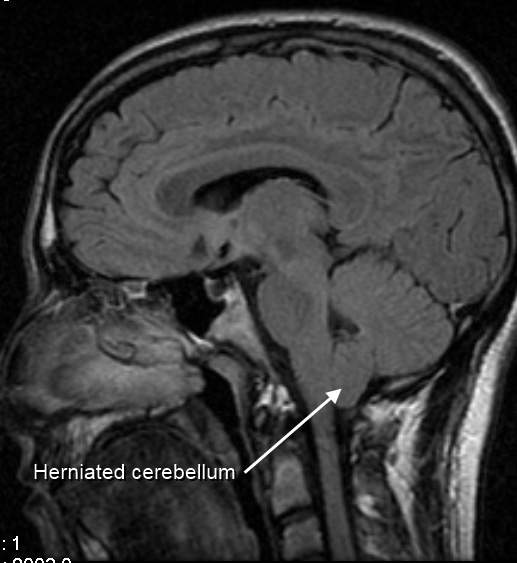

Arnold Chiari Malformation

Arnold-Chiari malformation is a condition in which the spinal canal is invaded by the lower section of the brain.

Arnold-Chiari malformation is a foramen magnum-based congenital expansion of the cerebellar tonsils.

Hydrocephalus may develop in Arnold-Chiari malformation as a result of cerebrospinal fluid (CSF) flow obstruction.

Arnold-Chiari malformation may present together with meningomyelocele or syringomyelia.

• Arnold Chiari Malformation

Arnold Chiari Malformation. Syringomyelia associated with Chiari malformation © Nevit Dilmen Dichromatic, False-color MRI. Cervical spine, T1 Red, T2, Green& Blue Permission details You may select the license of your choice. Not altered. CC BY-SA 3.0